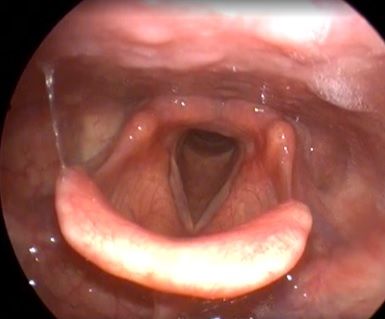

Клинический пример №2. Хирургическое лечение двустороннего паралича гортани с использованием лазера 445 нм.

Лечение данных пациентов в нашей клинике проводится по разработанному методу Кривопаловым А.А., д.м.н. зав. НИО патологии верхних дыхательных путей. Данная методика себя очень хорошо зарекомендовала.

После операции воспалительные проявления со стороны голосовой складки слабо выражены. Через месяц после операции пациенты готовы к следующему этапы реабилитации – занятие с фонопедом.

Рис 2А. Двусторонний паралич гортани. До операции.

Рис 2Б Двусторонний паралич гортани. 7 сутки после операции

Рис 2В Двусторонний паралич гортани. 1 месяц после операции